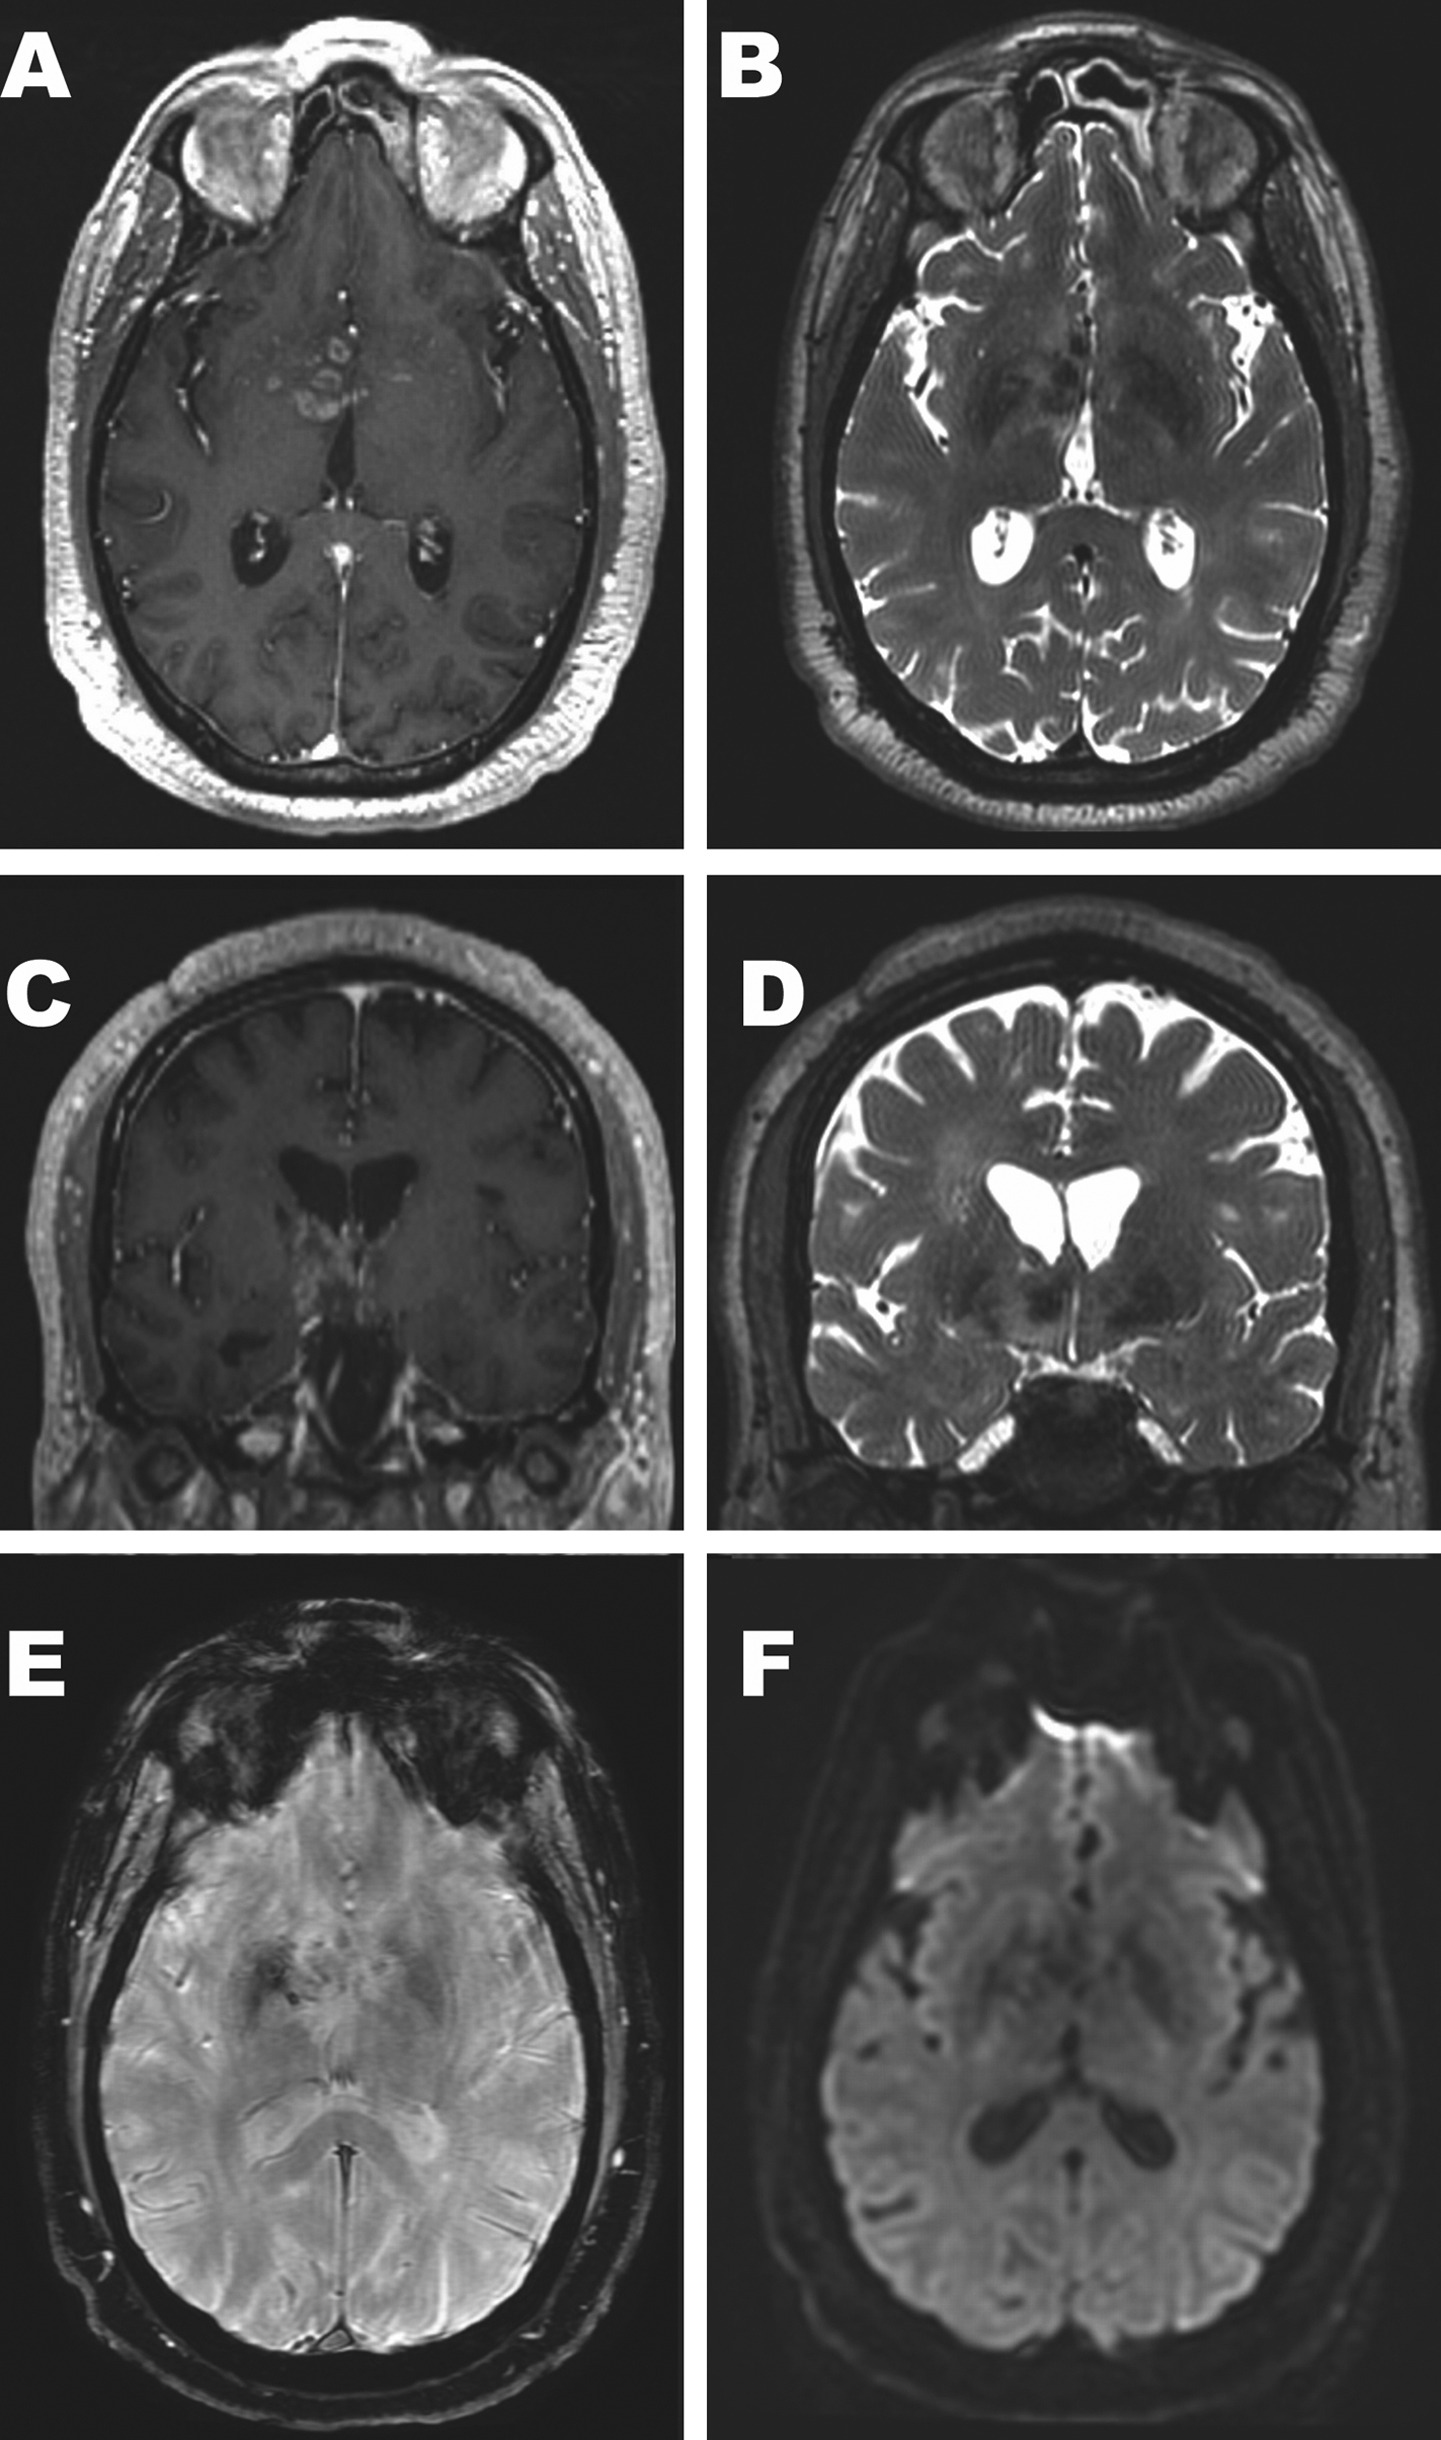

患者为56岁男性,因疲劳诊断为继发性甲状腺机能减退而进行MRI检查。其他垂体激素正常,脑脊液(CSF)分析正常。头颅MRI显示数个小的增强性结节病

灶,主要集中在右下丘脑区域,病灶周围可见T2高信号,第三脑室侧壁可见轻度占位效应(图1)。结节的增强模式为实性和环状,部分增强的结节呈T2低信号,ADC值增加;右侧豆状核内侧可见SWI低信号。沿延髓深静脉未发现SWI低信号。最初认为该表现提示淋巴瘤或肉芽肿性炎(如结节病)或肉芽肿性感染(如分枝杆菌)有关。PET-CT显示头部、胸部、腹部或骨盆的FDG摄取无病理性增加。CT未显示与病变相关的明显钙化。为了明确诊断,患者接受了右下丘脑病灶立体定向活检。

图1 患者头颅MRI影像结果。

轴位T1增强(A),轴位T2加权(B),冠状位T1增强(C)和冠状位T2加权(D)图像显示数个小的结节状T2低信号病灶,伴环形或实性增强,病灶主要分布在右下丘脑,少数在右侧腹侧丘脑和左下丘脑。第三脑室前部右侧可见轻度的占位效应。轴位SWI图像(E)显示右侧豆状核内侧不对称低信号,同一区域可见微小增强血管(A)。该区域的小血管在病理上钙化严重。弥散加权图像(F)没有显示出弥散受限。